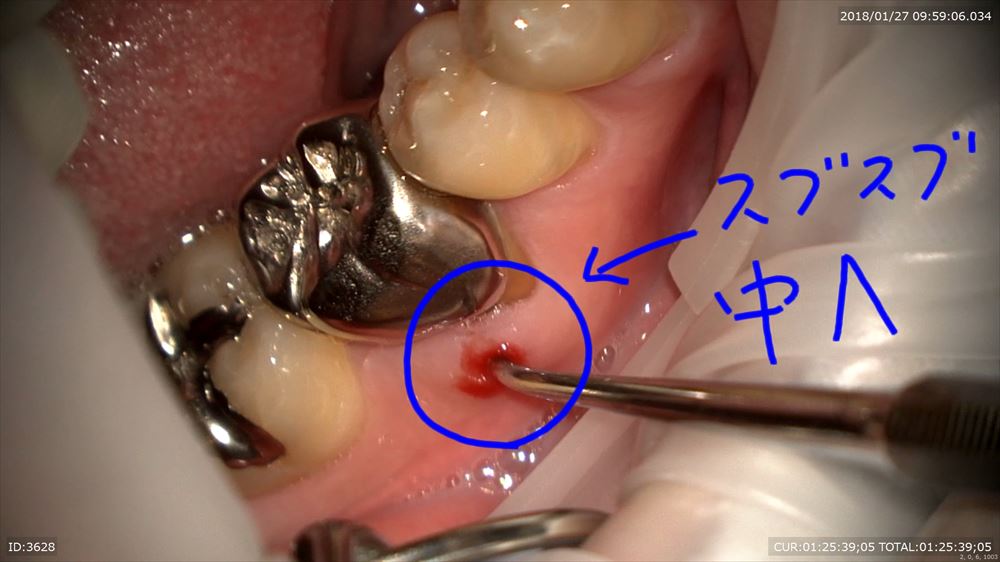

1つ目これがサイナストラクト

見えにくいですが穴が開いています。膿が出てきた!!CTでは約8mmの膿が確認。歯科ドック大切。